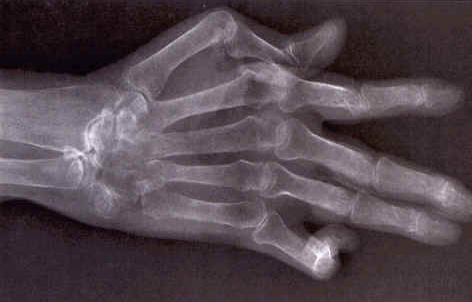

患上类风湿性关节炎会有哪些症状?

1、痛苦:关节痛苦是风湿病较常见的表现,全身关节都有也许发生痛苦,可是肢体和躯干部位的痛苦和也许导致内脏和神经系统的病变。